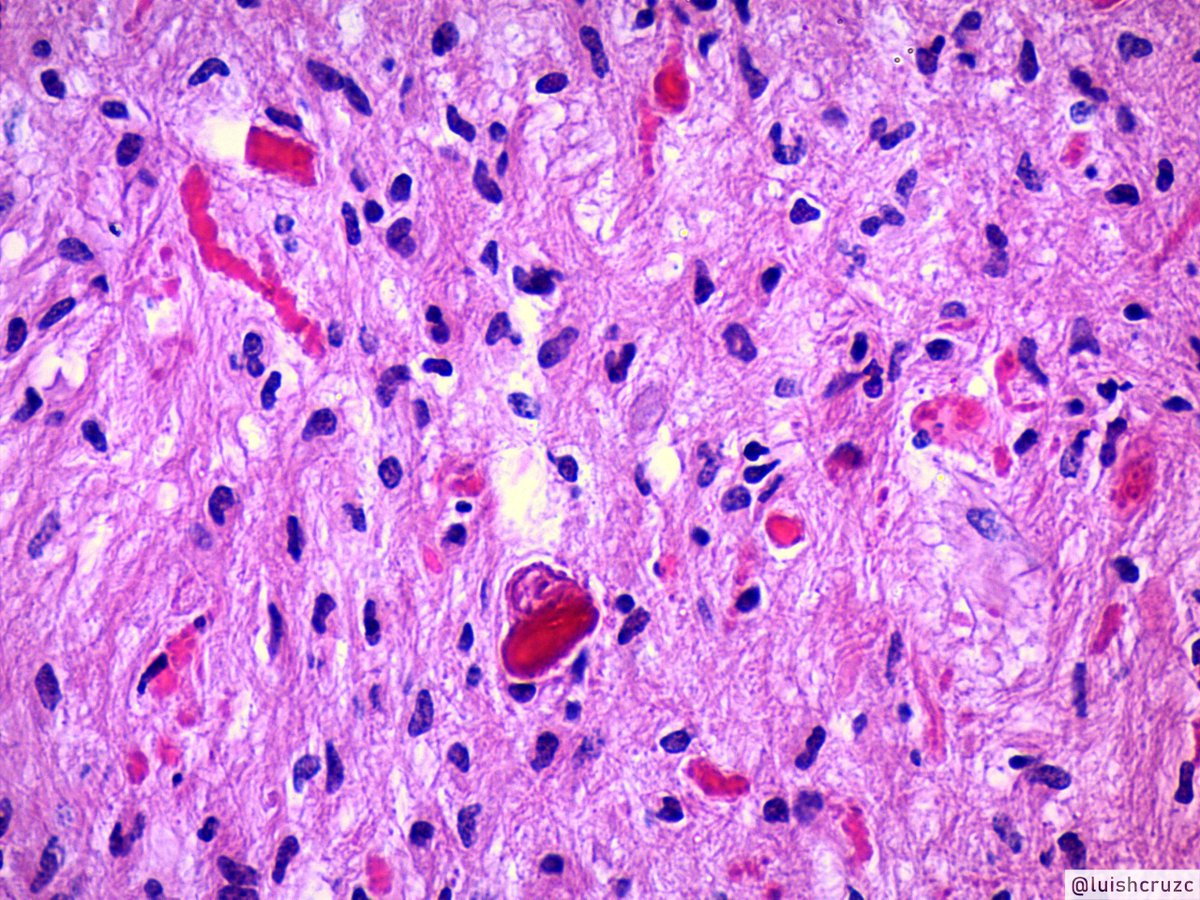

Микрофотографии гистологии глиобластомы головного мозга